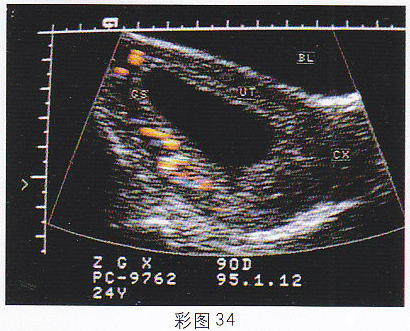

1.女,25岁,停经55天,腹痛、阴道出血1周。尿妊娠试验阴性。结合超声图像(彩图34),最可能的诊断为

正确答案:D 解题思路:宫腔内可见无回声暗区,其内未见胚芽及胎心搏动。患者有停经,腹痛,阴道流血等流产症状,尿HCG阴性。